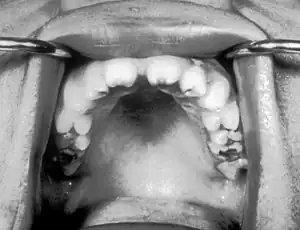

| Notched incisors known as Hutchinson's teeth which are characteristic of congenital syphilis | |

- Blunted upper incisor teeth known as Hutchinson's teeth

A frequently-found group of symptoms is Hutchinson's triad, which consists of Hutchinson's teeth (notched incisors), keratitis and deafness and occurs in 63% of cases.[18]

- Hutchinson's triad, a set of symptoms consisting of deafness, Hutchinson's teeth (centrally notched, widely spaced peg-shaped upper central incisors), and interstitial keratitis (IK), an inflammation of the cornea which can lead to corneal scarring and potential blindness